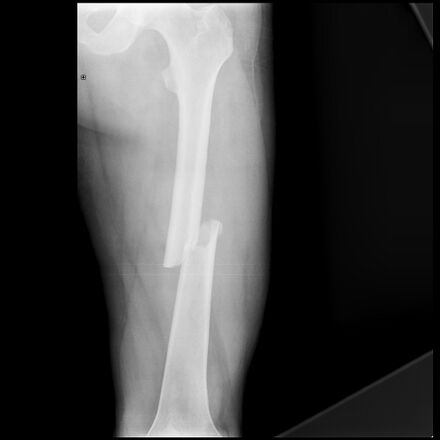

Стержень бедренной кости

Стержень бедренной кости почти цилиндрической формы, слегка шире в верхней части и слегка изогнутый, придавая ему выпуклость спереди и вогнутость сзади с заметным продольным выступом кости, линией аспера. Разнообразные мышцы начинаются и прикрепляются к стержню бедренной кости (все, кроме большой ягодичной и промежуточной широкой мышцы бедра, взаимодействуют с задней поверхностью кости).[4]